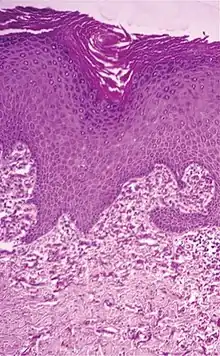

Histology

Elastic fibers stain well with aldehyde fuchsin, orcein,[16] and Weigert's elastic stain in histological sections.

The permanganate-bisulfite-toluidine blue reaction is a highly selective and sensitive method for demonstrating elastic fibers under polarizing optics. The induced birefringence demonstrates the highly ordered molecular structure of the elastin molecules in the elastic fiber. This is not readily apparent under normal optics.